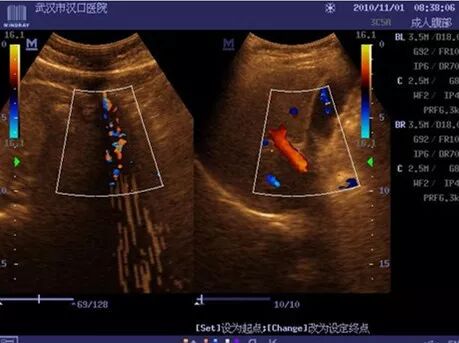

3、DC-6干扰

现象:二维图像波纹干扰;彩色取样框内条状干扰;

处理措施:更换发射板,故障解决。